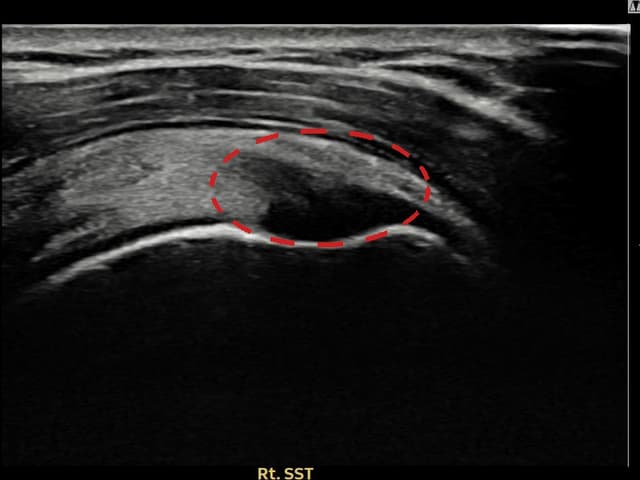

実際の患者様の施術前後の超音波画像。

手術なしで実現できる回復をご確認ください。

[経過期間: 24.04.26~24.07.05]

[縫縮術] 超音波検査にて右 棘上筋腱 관절면측 광범위 部分断裂(16mm × 5mm (腱厚の約75%欠損))を確認。縫縮術施行後、腱の連続性が回復し、日常生活に復帰されました。